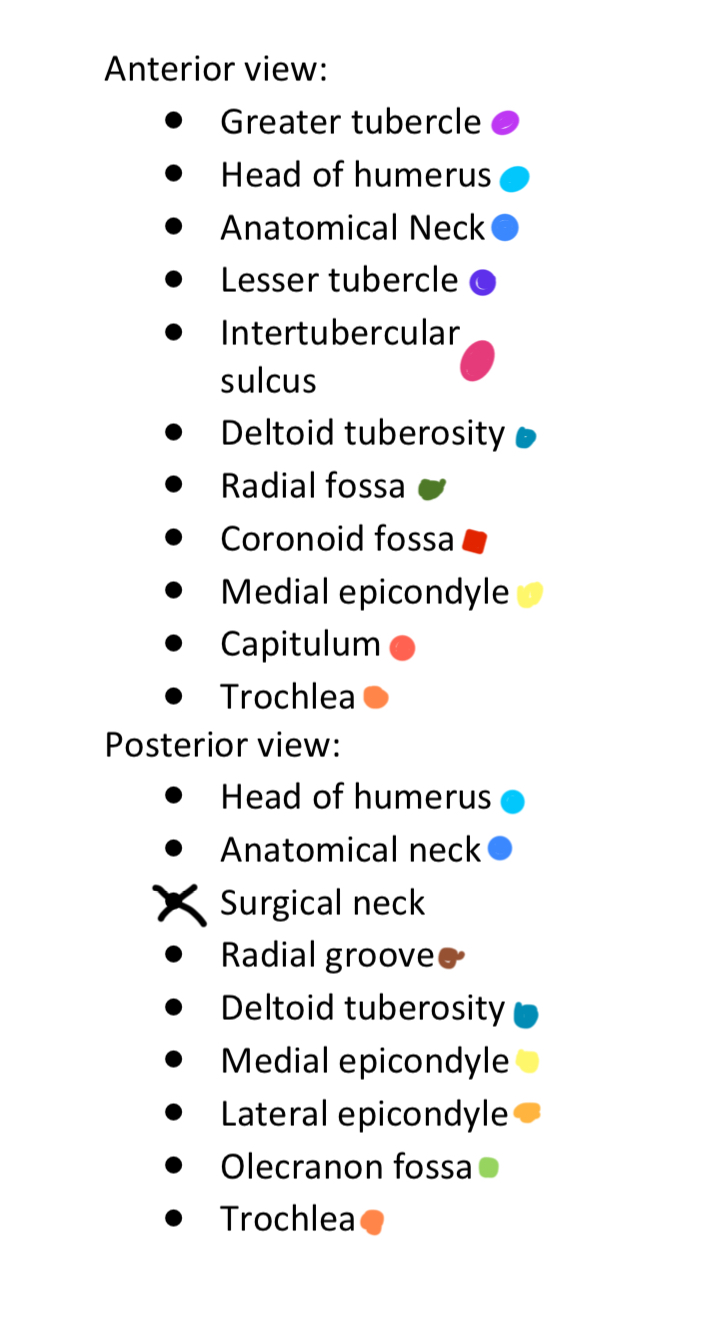

Anterior & Posterior Views of the Humerus

Light Purple

Greater Tubercle

2

New cards

Light Blue

Head of Humerus

3

New cards

Dark Blue

Anatomical Neck

4

New cards

Dark Purple

Lesser Tubercle

5

New cards

Pink

Intertubercular Sulcus

6

New cards

Cyan

Deltoid Tuberosity

7

New cards

Dark Green

Radial Fossa

8

New cards

Red

Coronoid Fossa

9

New cards

Yellow

Medial Epicondyle

10

New cards

Salmon

Capitulum

11

New cards

Dark Orange

Torchlea

12

New cards

Brown

Radial Groove

13

New cards

Light Orange

Lateral Epicondyle

14

New cards

Light Green

Olecranon Fossa